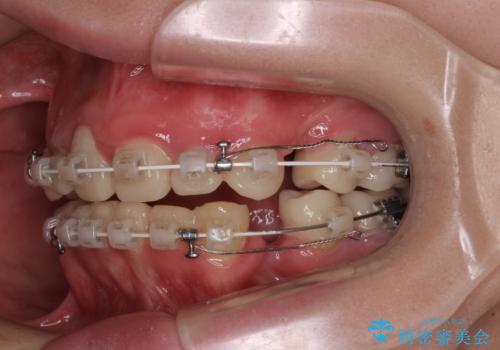

当初はほとんどの歯をむし歯治療のようにオールセラミッククラウンにて補綴治療を行う予定でしたが、仮歯に置き換えた時点で、口元の突出感や下顎前歯の叢生が気になるとのことで、上下左右の第一小臼歯4本を抜歯したワイヤー装置での抜歯矯正を行うこととしました。

矯正治療終了後に、残った歯をオールセラミッククラウンにて補綴治療を行うこととしました。

途中来院が困難な時期があったり、歯周外科処置を行って治癒を待ったりと、治療期間は長くなりましたが、初診時とは比べものにならないくらいきれいに仕上げることができました。